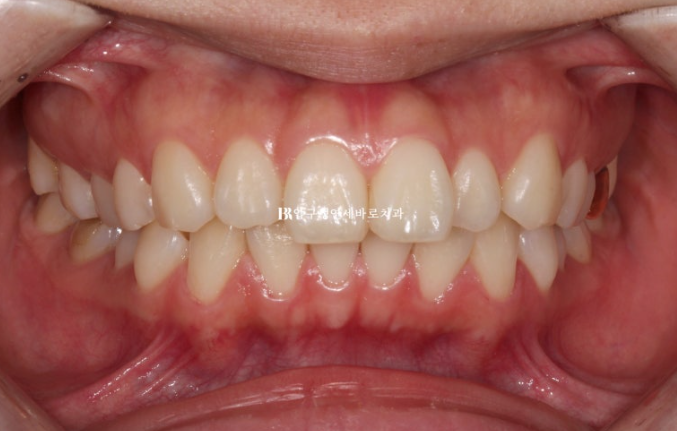

This patient came in June 2023 for protrusion and alignment improvement.

23.06

A mismatch in the midline is visible.

Because the upper front teeth protrude, the gap with the lower teeth is large.

If the front tooth bite is in this condition, the lips cannot close comfortably.

This can cause lip incompetence.